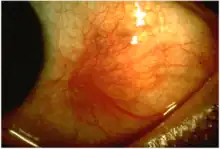

Scleritis is a serious inflammatory disease that affects the white outer coating of the eye, known as the sclera. The disease is often contracted through association with other diseases of the body, such as granulomatosis with polyangiitis or rheumatoid arthritis. There are three types of scleritis: diffuse scleritis (the most common), nodular scleritis, and necrotizing scleritis (the most severe). Scleritis may be the first symptom of onset of connective tissue disease.[1]

- Redness of the sclera and conjunctiva, sometimes changing to a purple hue

The pain of episcleritis is less severe than in scleritis.[4] In hyperemia, there is a visible increase in the blood flow to the sclera (hyperaemia), which accounts for the redness of the eye. Unlike in conjunctivitis, this redness will not move with gentle pressure to the conjunctiva.

Scleritis is best detected by examining the sclera in daylight; retracting the lids helps determine the extent of involvement. Other aspects of the eye exam (i.e. visual acuity testing, slit lamp examination, etc.) may be normal. Scleritis may be differentiated from episcleritis by using phenylephrine eye drops, which causes blanching of the blood vessels in episcleritis, but not in scleritis.[4]